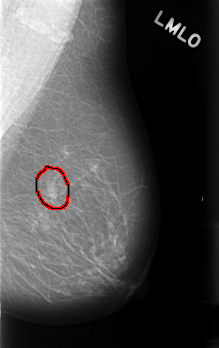

C_0454_1.LEFT_MLO

FILE: C_0454_1.LEFT_MLO.OVERLAY

TOTAL_ABNORMALITIES 1

ABNORMALITY 1

LESION_TYPE MASS SHAPE OVAL MARGINS CIRCUMSCRIBED

ASSESSMENT 3

SUBTLETY 5

PATHOLOGY BENIGN_WITHOUT_CALLBACK

TOTAL_OUTLINES 1

BOUNDARY